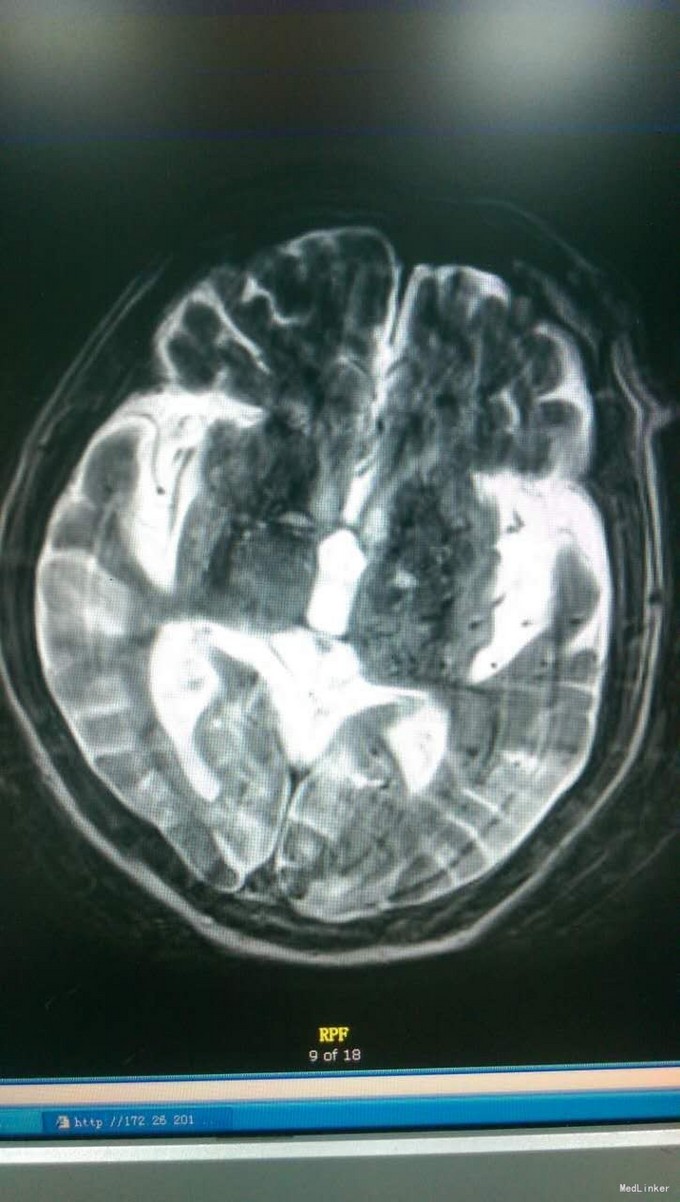

体格检查:T:36.2℃,P:79次/分,R:16次/分,BP:108/60mmHg。皮肤巩膜无黄染,无瘀点瘀斑。浅表未触及肿大淋巴结,肺部听诊双肺呼吸音清,未闻及干湿啰音,心律齐,各瓣膜听诊区未闻及病理性杂音,腹软,无压痛,肝脾肋下未触及,双下肢无浮肿,足背动脉博东良好。 专科查体:神志清醒,查体欠合作,言语正常,发音构音不良。双瞳孔等大正圆,D≈3.0mm,光反应灵敏。双眼向各方向运动充分,无眼震。无面舌瘫。颈强阴性。四肢肌力V级,四肢肌张力正常。BCR(L:++,R:++),TCR(L:++,R:++),PSR(L:++,R:++),ASR(L:++,R:++)。Babinski征(L:±,R:±)。深浅感觉查体未见确切异常。共济运动双侧稳准。 辅助检查:头CT(我院门诊,11-23)脑内多发软化灶。老年性脑萎缩。颈后部皮下血肿

初步诊断:血管性认知功能障碍 脑梗塞后遗症 高血压3级(极高危险组)2型糖尿病 冠心病 诊断依据:1、患者既往多发脑梗塞病史;此次以”糊涂5个月,加重半月余“为主诉入院,血管性认知功能障碍2、患者5个月前患脑梗塞,当时右侧肢体活动不灵,遗留言语含糊。3、高血压病史10余年,最高可达180/90mmHg,口服美卡素80mg日一次控制在130-140/70-80mmHg。4、2型糖尿病10余年,拜糖平50mg日3次、格华止0.5g日3次餐中口服,近半年停用诺和灵30R皮下注射,控制不详。5、冠心病10余年,偶有心前区疼痛、胸闷发作,平日口服扩冠。 治疗计划:1、完善入院常规检查如血常规、血生化、头MRI+DWI及血管相关检查等 2、给予患者改善脑循环、抗血小板、营养脑神经、改善认知功能、营养心肌、控制血压、监测血糖等对症支持治疗。